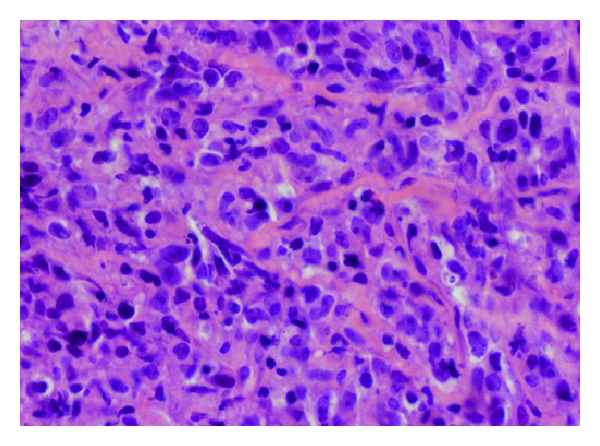

The patient is a 22-year-old woman who presented during the week 12 of her intrauterine pregnancy with one-month history of palpitations and intermittent chest pain, but no B-symptoms. The only abnormality on physical exam was a grade III/VI systolic murmur noted in the left upper sternal border. An echocardiogram revealed right ventricular systolic pressure of 60 mmHg, but normal left-ventricular ejection fraction. Blood tests revealed normal blood counts and chemistry, but an elevated lactate dehydrogenase at 1627 IU/L. An initial chest X-ray and follow-up computed tomography (CT) of the chest revealed a large mass in the mediastinum measuring cm extending into the left neck and compressing the main pulmonary artery. She thereafter underwent a CT-guided biopsy of the mediastinal mass that revealed large-sized cells associated with compartmentalizing alveolar fibrosis (Figure 1(a)) that were positive for CD20, CD30 (Figures 1(b) and 1(c)), and CD45 and negative for CD3, CD10, CD15, CD34, TdT, CD23, MUM-1, and keratin. A diagnosis of PMLBCL was established. A bone marrow biopsy showed no immunophenotypic evidence of malignant involvement. Because of her pregnancy, her abdominal staging was done with a magnetic resonance imaging (MRI) of the abdomen and pelvis that found no abnormalities. She was staged as stage IIA PMLBCL with bulky disease in the mediastinum.

The disease often presents as a bulky tumor in the mediastinum, causing compressive symptoms including dyspnea and superior vena cava syndrome. Pleural or pericardial effusions have been found at presentation in up to 50% of patients. While bone marrow infiltration is rare, extranodal sites may be involved in recurrent disease [8]. PMLBCL arises from a population of thymic B cells and consists of medium-sized to large cells with an abundant pale cytoplasm and they are commonly associated with a delicate interstitial fibrosis. Immunohistochemistry of the cells shows the presence of B-cell antigens, including CD19, CD20, CD22, and CD79a, in addition to CD30 positivity in more than 80% of cases [8]. While genomic profiling has allowed PMLBCL to be distinguished from DLBCL, it has also demonstrated similarities between the transcription profile of PMLBCL and Hodgkin lymphoma. Specifically, over one-third of all PMLBCL signature genes, including MAL, SNFT, TNFRSF6, TARC, and CD30, were found to be highly expressed in the Hodgkin lymphoma [9].